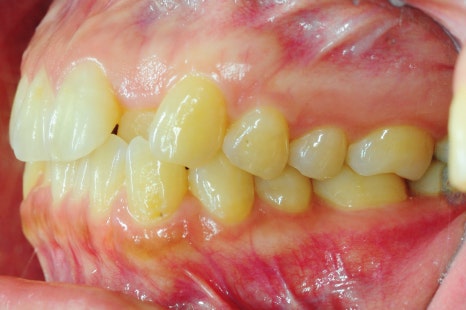

인비절라인 8개월 교정 전후 모습

*치료 기간: 2024.04.21 - 2024.12.22

*치료 전후 사진은 환자의 동의하에 게재하였으며, 동일한 환경과 조건에서 촬영된 전후 사진입니다.